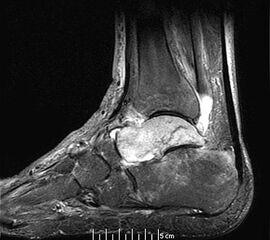

Häufigste Prädilektionsstelle am Fuß stellt der Talus dar, wobei gelegentlich auch der Kalkaneus mitbefallen ist. Einzelne Fallbeschreibungen gibt es zum TKMÖ der Cuneiforme und des Os navikulare (Abb. 1), Studien zum Befall des Vorfußes liegen nicht vor 9.

Mitunter kommt es im Krankheitsverlauf zur verzögerten Migration des Ödems in benachbarte Skelettabschnitte (z.B. Migration vom Talus in die distale Tibia oder in den Kalkaneus) (Abb. 2 und 3), was den Krankheitsverlauf erheblich prolongieren kann.